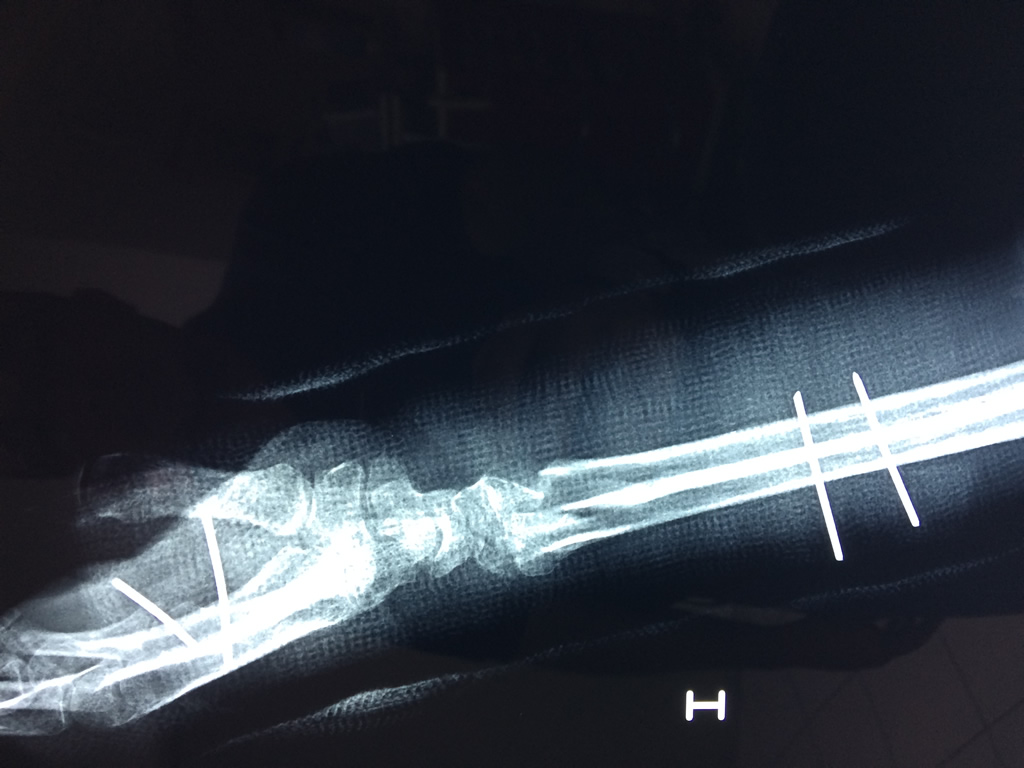

Cirugías de Muñecas

Los procedimientos más comunes en cirugía de la mano son aquellos destinados a reparar traumatismos, incluyendo lesiones de tendones, nervios, vasos sanguíneos, y articulaciones; huesos fracturados; y quemaduras, cortes, y otros daños de la piel.